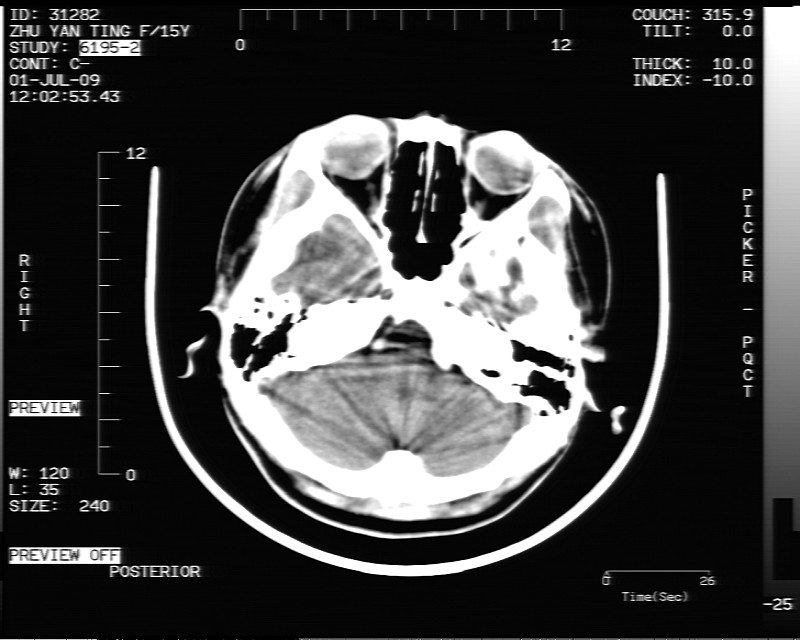

以下是引用随光逐影在2009-7-1 16:26:00的发言:[br]鞍上池表皮样囊肿或含脂肪类肿瘤破裂并化学性脑炎?

以下是引用余辉在2009-7-1 17:20:00的发言:[br]病变ct值-20至-80[br]考虑脑内脂肪瘤破裂,瘤主体应该在右侧桥小脑角池及鞍上池[br]鞍上池病灶面积较大,ct值应该能够测准,应此病灶应该就是脂肪密度,病灶密度有ct值-20至-80hu,为成熟脂肪密度,因此考虑脂肪瘤,也不除外其他含成熟脂肪的病灶[br]皮样囊肿密度应该稍高一点

以下是引用zjzjr在2009-7-1 16:52:00的发言:[br]支持皮样囊肿破裂.,表皮样囊肿一般密度均高.[br][br][本贴已被 zjzjr 于 2009-7-1 16:52:29 修改过]